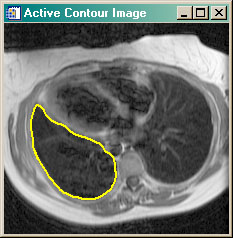

- cgSNAKE Applies active contouring Gradient Vector Flow "snake" contour algorithm to 2D dataset.

cgSNAKE | |

This program is similar to the

ActiveContour program in that it implements the Gradient Vector Flow

active contouring method of Xu and Prince. It differs in that it does so without

requiring an interactive GUI. In other words, the GVF algorithm can be applied to

a 2D dataset as a function, in the manner of other image processing functions.

The program requires that the GVF_Snake program be purchased from the Coyote Store. You can read more about active contouring in the article Active Contouring (Snakes) in IDL. |